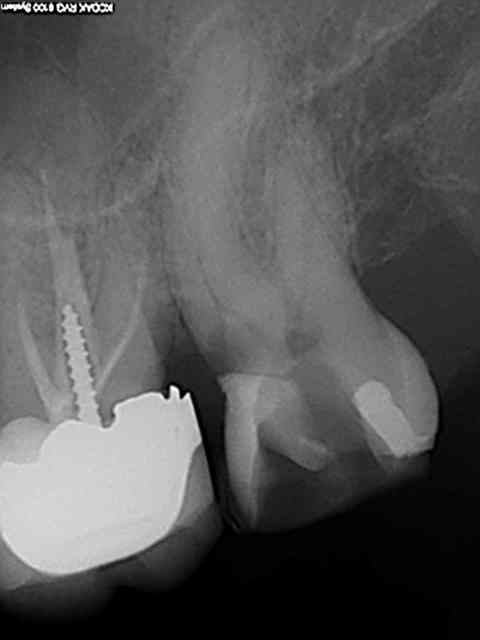

Exemple concret, de ce samedi (exceptionnellement au boulot car c'est un pote qui travaille sur Paris et qui a une semaine de vacances), j'en ai tous les jours.

la première radio date de 2011 issue d'un status inutile selon la sécu. Suspicion de reprise en mésial sous l'onlay de 27, noté sur le dossier à surveiller. Le patient appelle pour douleurs lancinantes spontanées la semaine dernière en haut au fond et à gauche exacerbées par le froid.

Diagnostic clair net et précis et par téléphone en plus : ca n'est pas du au tt merdique de la 26. Ce qui est confirmé in situ par la radio numéro 2 prise le jour meme de l'endo.

Comme à mon habitude je m'excuse d'avoir irradié le patient copieusement ( à raison de 70 kv et 0,099 s par cliché) plutot qu'un seul cliché argentique en fin de tt ( 70 kv aussi mais 1,3 s d'exposition lui) développé en fin de journée comme ca a du etre le cas pour le tt de 26 ( et m... encore raté).

Je sais pas moi mais le résultat parle de lui meme ( putain de mv2 que j'ai réussi à choper dans un 2 eme temps une fois les autres obturés)

Taille empreinte provisoire dans la foulée , l'avantage de la gutta chaude.

Vous préférez quoi dans votre bouche ? une seule radio et un tt endo comme la 26 ou 6 clichés et mon tt endo de 27 ?